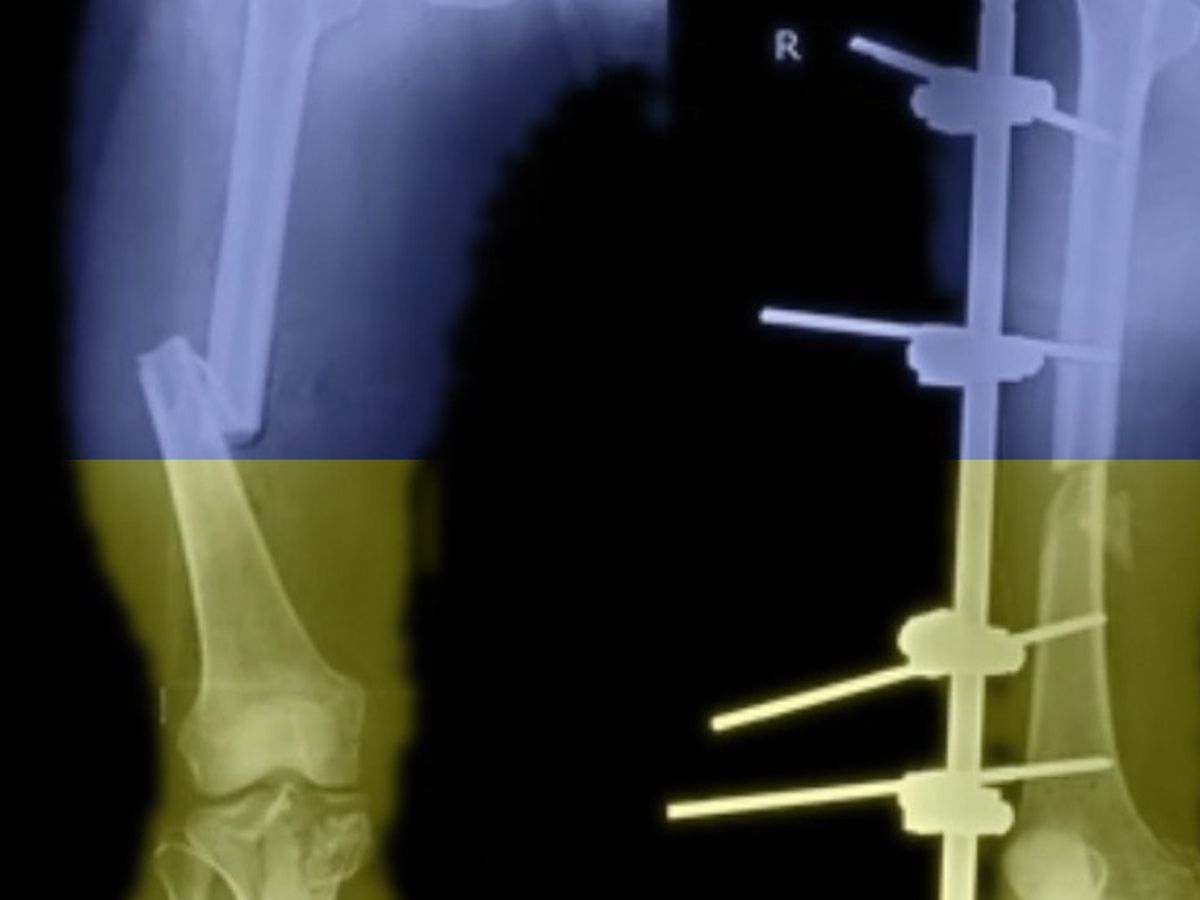

unsere unfallchirurgischen Kolleginnen und Kollegen in der Ukraine benötigen dringend weitere und vor allem zielgerichtete Unterstützung! Jeder von uns kennt das, wenn man operieren will, das aber nicht kann, weil die Implantate fehlen. In der ohnehin schon schwierigen Lage kämpfen unsere Kollegen in der Ukraine mit diesem Problem täglich.

Unsere unfallchirurgischen Kollegen in der Ukraine bitten dringend um Fixateure, um die vielen offenen Verletzungen behandeln zu können. Deswegen sammeln wir Geld, um eine große Anzahl an Fixateur-Material zu kaufen und über die bereits gut funktionierenden Lieferketten direkt an die Zielkliniken zu liefern (genauere Infos zu bereits erfolgen Hilfsaktionen s. AG Ukrainehilfe Medizinerschaft Regensburg).